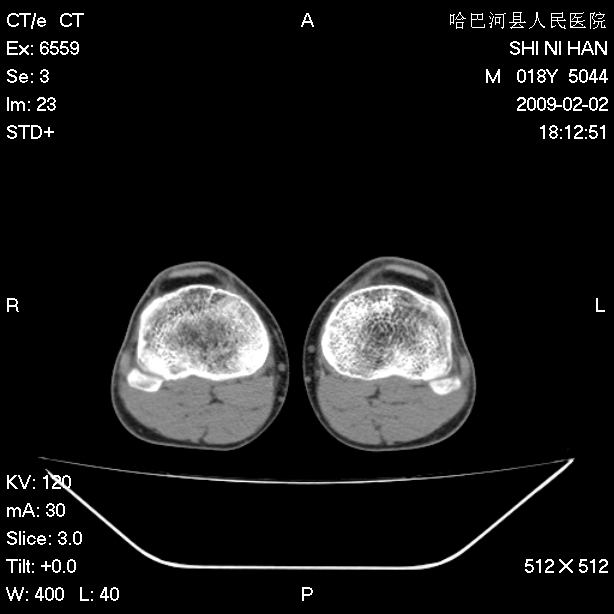

标题: CT17889:外伤后右膝关节反复疼痛3年余 [打印本页]

标题: CT17889:外伤后右膝关节反复疼痛3年余

mri检查,看看半月板情况如何。

可能韧带有问题!

ct未见明显异常。关节腔未见明显积液,半月板未见明显撕裂。但最好还是mri看看韧带及半月板情况。